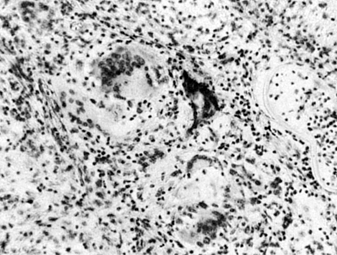

4. SYMPATHETIC OPHTHALMIA (Figure 7-6)

Figure 7-6

Figure 7-6: Microscopic section of giant cells and lymphocytes in sympathetic ophthalmia involving the choroid. (Courtesy of R Carriker.)

The injured, or exciting, eye becomes inflamed first and the fellow, or sympathizing, eye secondarily. Patients usually complain of photophobia, redness, and blurred vision though the presence of floaters may be the primary complaint. The uveitis is usually diffuse. Soft yellow-white exudates in the deep layer of the retina (Dalen-Fuchs nodules) are sometimes seen in the posterior segment. Serous retinal detachments also occur.

The recommended treatment of a severely injured sightless eye is enucleation within 10 days after injury. The sympathizing eye should be treated aggressively with local or systemic corticosteroids. Other immunosuppressive agents such as cyclosporine, cyclophosphamide, and chlorambucil may be required as well (see Table 7-2). Without treatment, the disease progresses relentlessly to complete bilateral blindness.